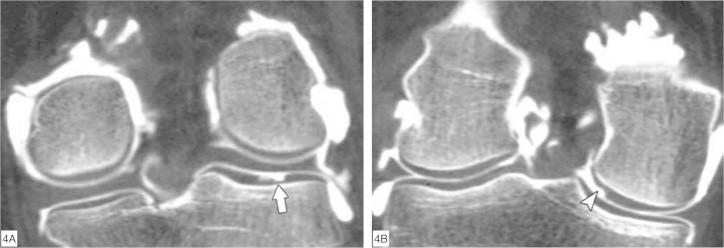

Through the ability of magnetic resonance imaging (MRI) to characterize soft tissue noninvasively, it has become an excellent method for evaluating cartilage. The development of new and faster methods allowed increased resolution and contrast in evaluating chondral structure, with greater diagnostic accuracy. In addition, physiological techniques for cartilage assessment that can detect early changes before the appearance of cracks and erosion have been developed. In this updating article, the various techniques for chondral assessment using knee MRI will be discussed and demonstrated.